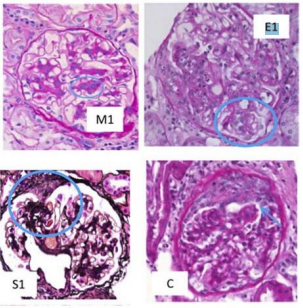

Um paciente de 32 anos de idade foi diagnosticado,

recentemente, com hipertensão de diagnóstico (PA =

160 mmHg x 90 mmHg) e hematúria microscópica repetida e

confirmada. Exames complementares revelaram creatinina

sérica = 1,0 mg/dL e proteinúria na urina de 24 horas =

650 mg. Ele foi submetido a biópsia renal, segundo a figura

apresentada, que confirmou o diagnóstico de nefropatia por

IgA com pontuação MEST-C M1, E1, S1, T1, С.

Um paciente de 32 anos de idade foi diagnosticado,

recentemente, com hipertensão de diagnóstico (PA =

160 mmHg x 90 mmHg) e hematúria microscópica repetida e

confirmada. Exames complementares revelaram creatinina

sérica = 1,0 mg/dL e proteinúria na urina de 24 horas =

650 mg. Ele foi submetido a biópsia renal, segundo a figura

apresentada, que confirmou o diagnóstico de nefropatia por

IgA com pontuação MEST-C M1, E1, S1, T1, С.